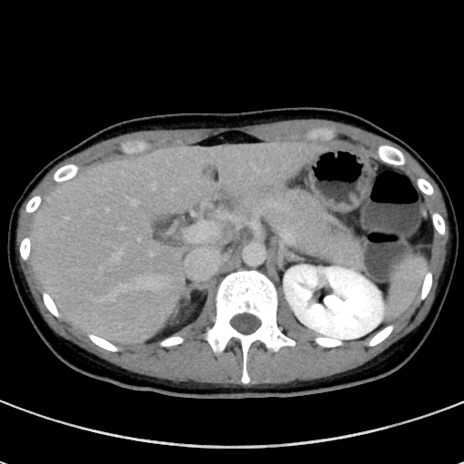

冠状断像

【症例】20歳代女性

【主訴】嘔吐、下腹部痛

【現病歴】昨日夕食後に嘔吐し下腹部痛が出現。本日になっても嘔吐持続し改善しないため来院。

【身体所見】意識清明、BT 37.2℃、BP 108/67mmHg、腹部:平坦、やや硬、下腹部正中から右にかけて圧痛あり、反跳痛軽度あり、tapping pain(+)。

【データ】WBC 13600、CRP 14.94